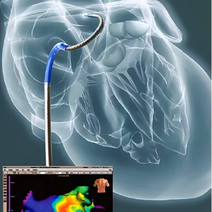

冠状动脉造影术的操作技巧- 4.8共8页

- 冠状动脉造影术的操作技巧姓名:考号:一、单选题(共10题)1在进行冠状动脉造影术时,正确的导管插入位置是A股动脉B股静脉C静脉D动脉2冠状动脉造影术中最常用的造影剂是什么A生理盐水B碘对比剂C葡萄糖D肝素3在进行冠状动脉造影术时,导管推进的技巧是什么A快速推进,避免损伤血管B缓慢推进,避免损伤血管C逆时针旋转推进